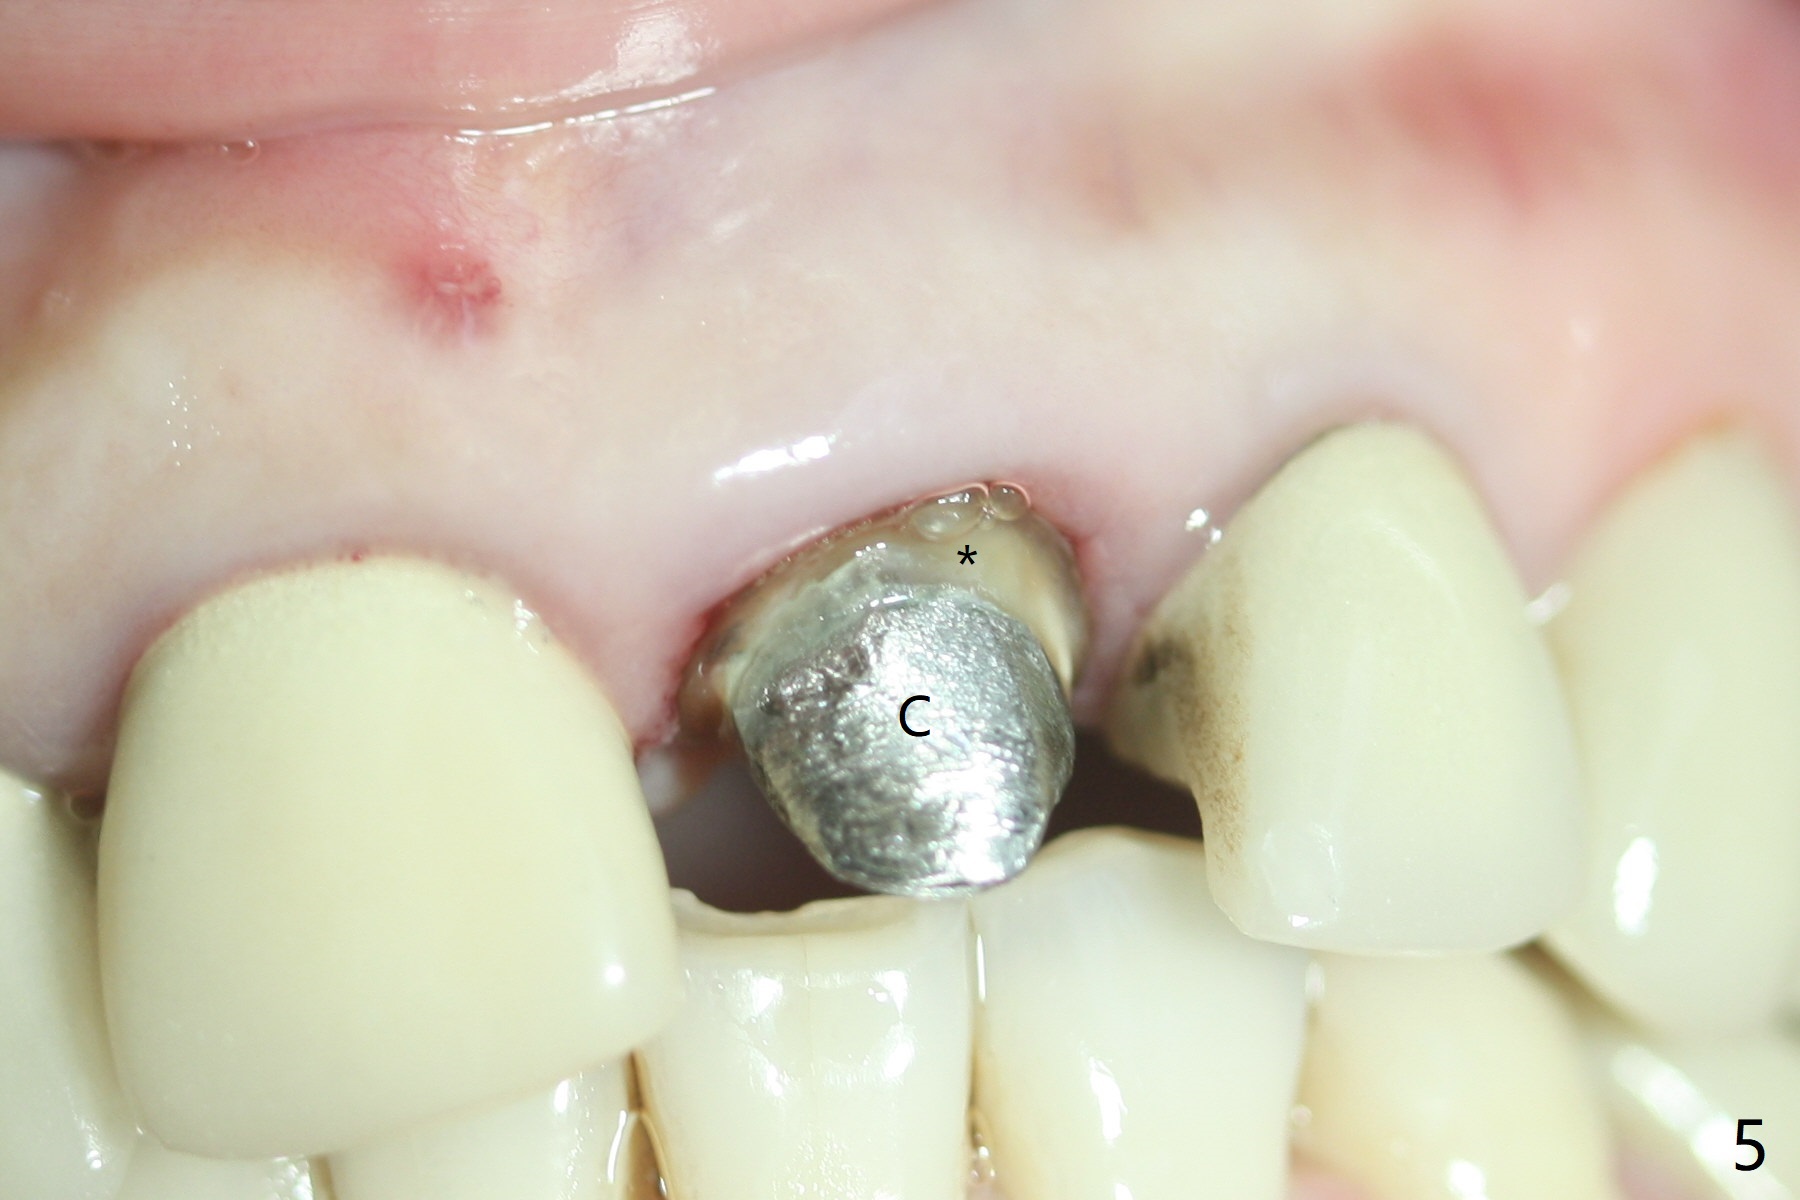

A 51-year-old woman with poor dentition has history repeated dislodged crown and post at #9. Finally the post fracture (Fig.1). After discussion of treatment options, she chooses to save the tooth. Treatment plan is to remove post, possible RCT retreatment, redo post and crown. The post remains stable following lengthy use of Piezo scaler (Fig.2). It appears that Piezo is quite aggressive, removing the tooth structure and the metal. Finally the coronal portion of the post is removed for cast post (Fig.3). There is approximately 2 mm for ferrule effect (Fig.4). The cast post is cemented with RelyX Ultimate and prepared for crown (Fig.5-7).